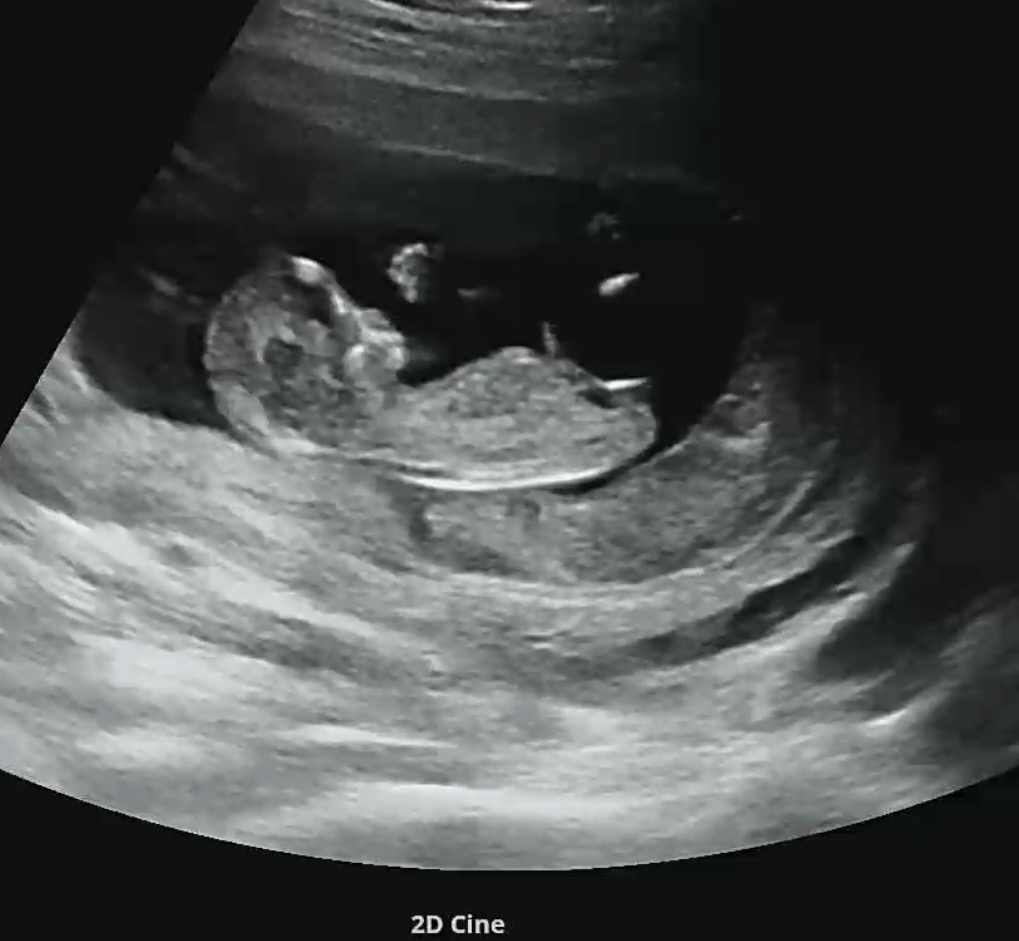

12주 각도법 고수님!!

12주차 성별 먼저 알려주실분!!!